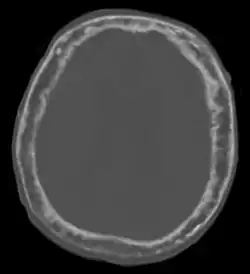

| "This 92 year-old male patient presented for assessment of sudden inability to move half his body. An incidental finding was marked thickening of the calvarium. The diploic space is widened and there are ill-defined sclerotic and lucent areas throughout. The cortex is thickened and irregular. The findings probably correspond to the 'cotton wool spots' seen on plain films in the later stages of Paget's disease." | |